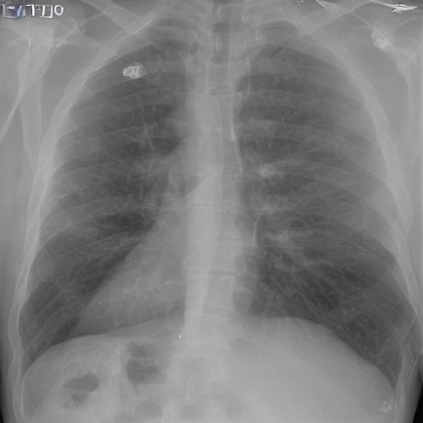

To address these issues, we propose a novel Adaptive patch-word Matching (AdaMatch) model to correlate chest X-ray (CXR) image regions with words in medical reports and apply it to CXR-report generation to provide explainability for the generation process. AdaMatch exploits the fine-grained relation between adaptive patches and words to provide explanations of specific image regions with corresponding words. To capture the abnormal regions of varying sizes and positions, we introduce the Adaptive Patch extraction (AdaPatch) module to acquire the adaptive patches for these regions adaptively. In order to provide explicit explainability for CXR-report generation task, we propose an AdaMatch-based bidirectional large language model for Cyclic CXR-report generation (AdaMatch-Cyclic). It employs the AdaMatch to obtain the keywords for CXR images and `keypatches' for medical reports as hints to guide CXR-report generation. Extensive experiments on two publicly available CXR datasets prove the effectiveness of our method and its superior performance to existing methods.